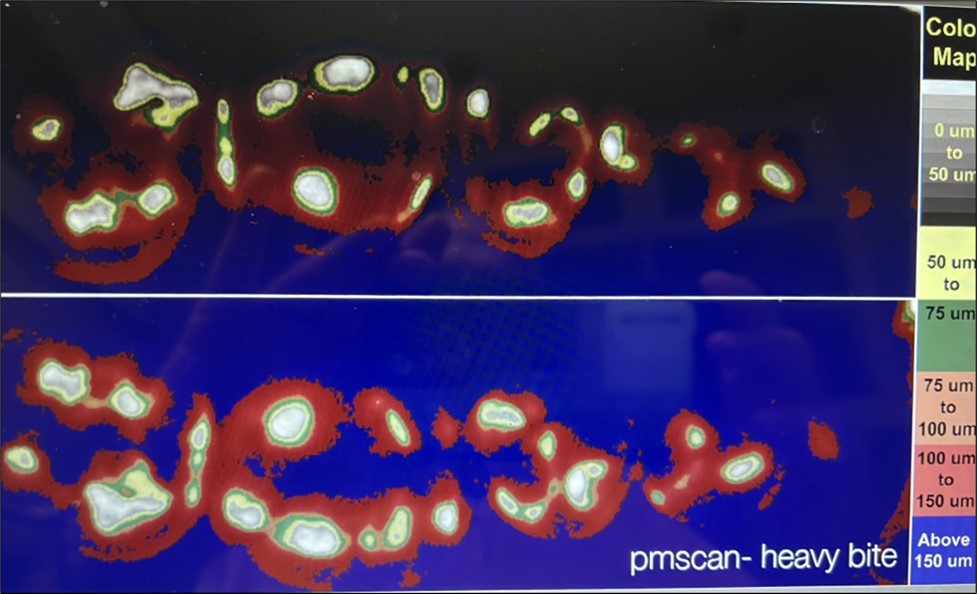

This observational study compares four clinically used methods for recording occlusal contacts. Recordings were made using each of four different methods on the same subject who volunteered participation. All recordings were made in office by one clinician (CS) during the same time period. A clinical subject with few restorations was selected and the subject agreed to the procedure along with the right to publish the results. There are no quantitative measurements. Ankylosis is a factor that was not addressed. The recording indicator systems evaluated were: 1. Accufilm (Parkell, Brentwood NY. USA). 2. Blue paper (Bausch, Nashua NH. USA), 3. Primescan (Densply/Serona, Waltham MA. USA), 4. PMscan (Mco, Boston MA. USA). In all procedures the subject was advised on how to close and the procedure was repeated. The subject made one hard closure into or onto the marking surface and the results were recorded and are displayed in (Figure 1) (Figure 2, Figure 3, Figure 4 )

Material 4: PMscan {Figure 4} records the occlusion in a non-set translucent silicone impression material which is loaded into a triple tray impression carrier. Intensity and movement for full arch can also be recorded and measured in millimeters. Records can be stored. The recording is instant. It is developed digitally with PMscan 2 which is comprised of a closed light box, a digital camera, an image analyzer (Image J) and a processor 11. Total time for recording and processing is one minute.

All materials and systems differ as do the recordings. Bite intensity is difficult to record except with the PMscan which also records infra occlusion 10. The figures suggest that intensity is important in aligning implant restorations and in monitoring bruxism and clenching pathologies 11. Paper and film do not record intensity and their markings are not permanent. Primescan requires a CAD system and does not record intensity or movement. PMscan records intensity and movement. The relation of occlusal contact to touch is unknown. What is evident is that the older systems may not fit present needs. New restorative procedures, techniques and repair systems require monitoring systems that fit the demands of today. Contact, intensity and permanent multidimensional recording systems are essential. The understanding of occlusion remains elusive.